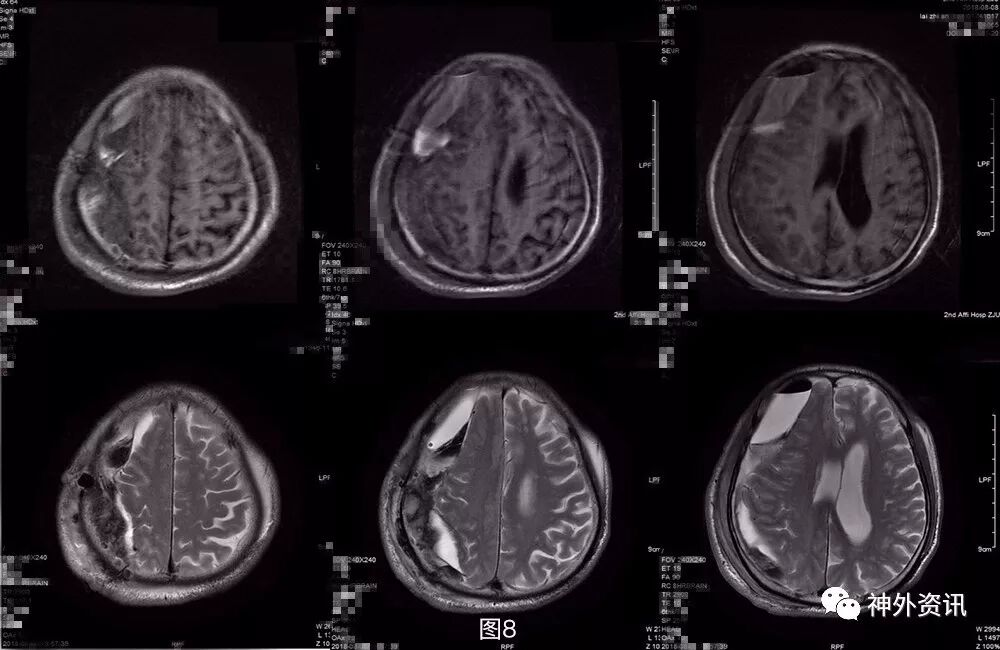

术后第3天患者出现意识变差及左肢体肌力进一步下降,查体:嗜睡,GCS14分,双侧瞳孔等大等圆,对光反应灵敏,左侧肢体肌2级,右侧肢体肌力5级,病理征未引出。急诊头颅CT提示局部积血积气积液较前片似有增多(图8)。与家属言明再次手术指征,风险及并发症等,家属要求保守,暂不手术。遂予以加用脱水药物及阿托伐他汀保守治疗。

图8. 第三次术后第3天头颅CT提示:局部积血积气积液较前片似有增多。